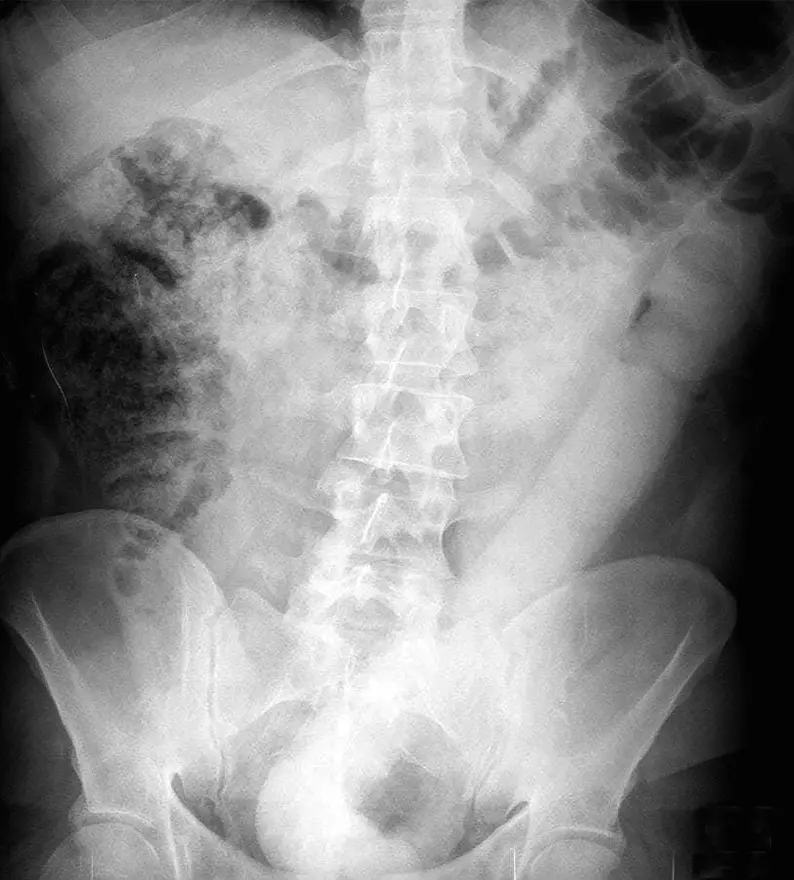

Un milanais de 31 ans s’est présenté aux urgences de Niguarda pour un problème de taille : celui-ci s’était introduit dans le rectum un godemiché de 60 centimètres de long, qu’il ne parvenait plus à extraire. Du fait du diamètre de l’objet, mais également de son volume et de sa rigidité, les urgentistes échouèrent également dans leurs tentatives (pince d’extraction de polypes, pince à biopsies…).

Radiographie du patient (le cliché de droite est une version retraitée de l'image, mettant en évidence le volumineux corps étranger).

Crédits : BMJ Case Reports / Lionel Conte.